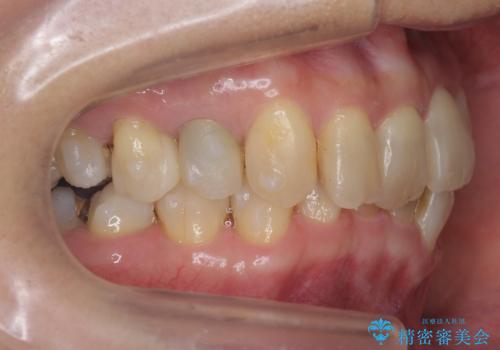

反対咬合や、すれ違い咬合もあり、大変難しいケースでしたが治療することができました。

かみ合わせが深い方はもともとかみしめが強く、マウスピース矯正を長期にすると、奥歯が咬まなくなってくる症状が強くなります。

今回もそういった状態になったのを、装着時間や歯の移動を工夫する形で治療しました。